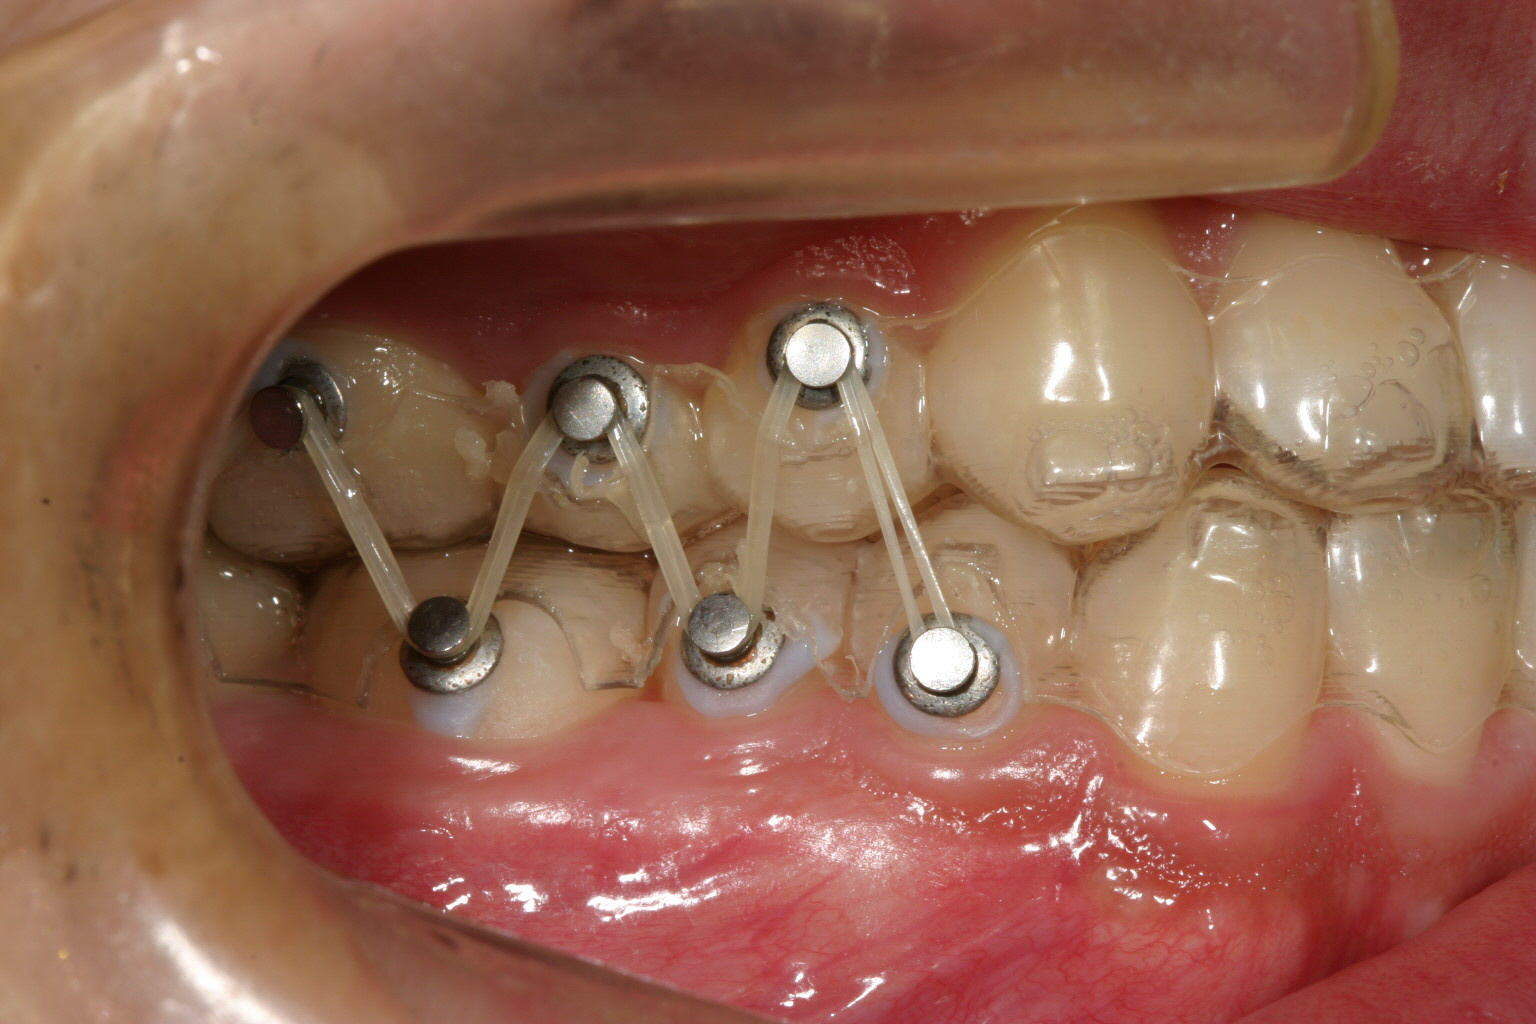

奥歯のかみ合わせを緊密にするためこの様なアップダウンエラスティックを使用しました。 その際も元々少ししゃくれ気味だったためCLASSⅢエラスティックとしています。

最終的に咬み合わせが少し甘いと感じた時はこの様なアップダウンエラスティックを使用致します。こうする事によりかみ合わせが緊密になります。